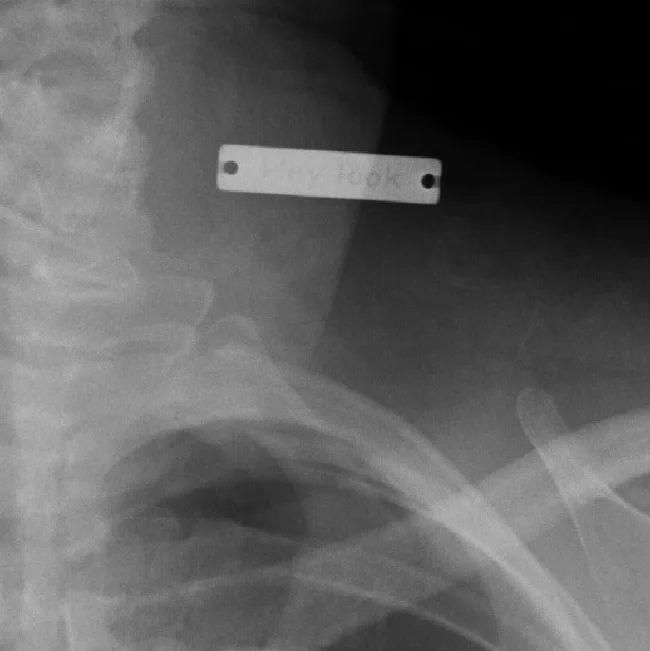

"Доктор удивился, увидев рентген"